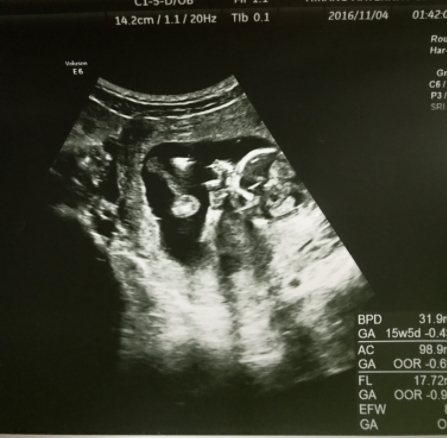

16週0日(16w0d・女の子)|yu0215ki さん(29歳)

エコー写真撮影時のエピソード:

パパも一緒にエコー見た!始めてのお腹からのエコー☆私よりパパの方が興奮してた(^O^)赤ちゃんは元気いっぱいで動き回ってた。手足を伸ばしたりして、背骨もしっかり出来てて順調で安心した( *ˊᵕˋ)

そして、今のところ女の子!でもまだへその緒で隠れてたりするからはっきり女の子とは言えないって^^でも元気で産まれてくれるならどっちでもいいや!